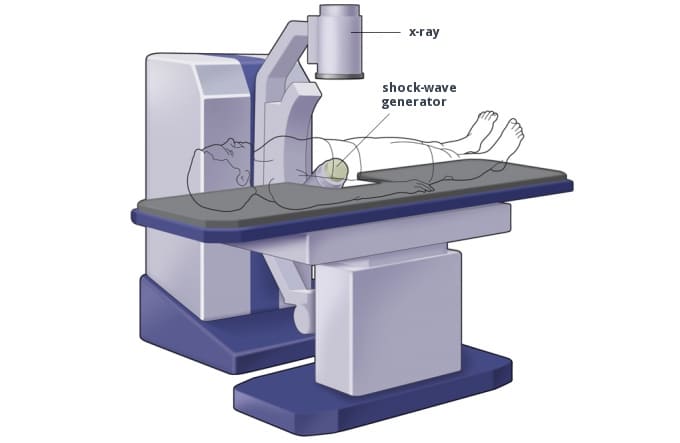

Εξωσωματική Λιθοτριψία κρουστικών κυμάτων (SWL)

Αυτή η διαδικασία (Εικ. 4&5), περιλαμβάνει τη χρήση ηχητικών κυμάτων από το εξωτερικό του σώματος για να διαλύσει ένα λίθο σε μικρότερα κομμάτια, τα οποία μπορούν στη συνέχεια να αποβληθούν φυσιολογικά με την ούρηση.

Η διαδικασία διαρκεί περίπου μία ώρα και είναι μετρίως επώδυνη. Για τον λόγο αυτό, χορηγείται φαρμακευτική παυσίπονη αγωγή. Λιγότερο συχνά, η διαδικασία της εξωσωματικής λιθοτριψίας γίνεται με νευρολήπτων αναισθησία (μέθη) με την παρουσία αναισθησιολόγου. Εάν πρόκειται για μια μεγάλη πέτρα, μπορεί να χρειαστούν αρκετές συνεδρίες για να θρυμματιστεί πλήρως.

Η λιθοτριψία κρουστικών κυμάτων δεν συνιστάται εάν:

- Είστε έγκυος

- Έχετε υψηλό κίνδυνο σοβαρής αιμορραγίας

- Έχετε οποιαδήποτε λοίμωξη

- Έχετε ανεξέλεγκτη υψηλή αρτηριακή πίεση

- Έχετε υψηλό δείκτη μάζας σώματος που σημαίνει ότι θα ήταν δύσκολο για τα ηχητικά κύματα να φτάσουν στην πέτρα λόγω της μεγάλης απόστασης από το δέρμα έως τον λίθο

- Έχετε ανεύρυσμα

- Έχετε απόφραξη στο ουροποιητικό σύστημα, κάτω από την πέτρα ή στην ουροδόχο κύστη

- Έχετε έναν πολύ σκληρό λίθο (λίθοι κυστίνης)

Εικ. 4: Εστιασμένα κρουστικά κύματα κατακερματίζουν λίθους σε μικρότερα θραύσματα

Εικ. 5: Ένας κοινός τύπος εξωσωματικού λιθοτρίπτη